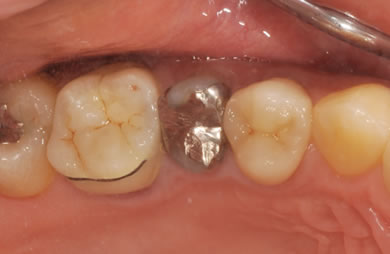

インプラントの症例写真 IMPLANT

骨再生インプラント治療+セラミック治療

| 治療方針 | 左側の奥歯の部分の歯が欠如しているのでインプラント治療にて機能的・審美的回復を行いつつ、その他の虫歯の部分はセラミック歯にて治療を行う。 | ||||||||||||||||||||||||||||||||

| 治療内容 | インプラント2本(ソケットリフト)、ハイブリッドセラミック2本、オールセラミック3本(オールセラミック用の土台3本)、メタルボンドセラミック2本(メタルボンドセラミック用の土台1本) | ||||||||||||||||||||||||||||||||

| 総治療費 | 1,662,900円 | ||||||||||||||||||||||||||||||||

| 治療期間 | 1年7ヶ月 |